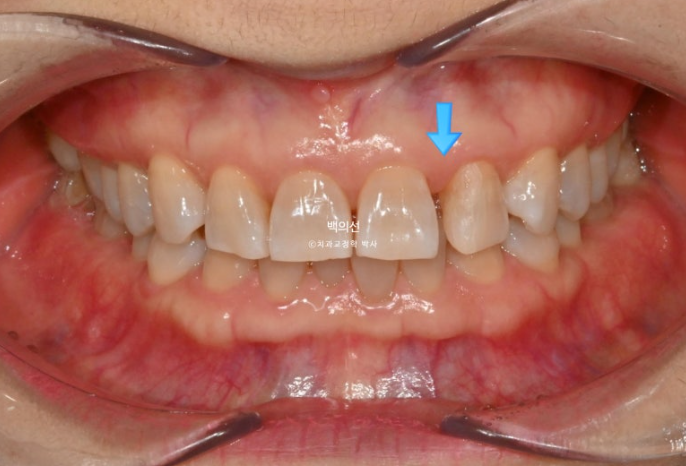

25년 2월, 교정치료를 위해 내원한 환자분입니다.

위 앞니 사이가 점점 벌어지고 아래 앞니는 점점 틀어진다 라는 이유로 오셨습니다.

25.02

앞니가 깊게 물리는 과개교합이 보입니다.

파란 화살표는 벌어진 틈을 레진으로 메꿔놓은 곳 입니다.